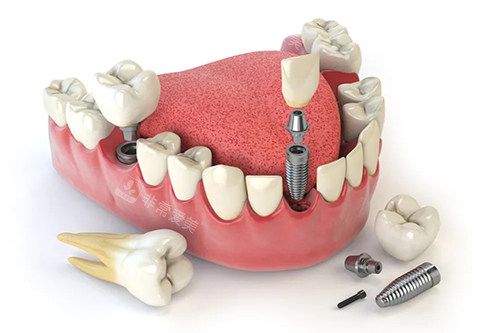

牙齿种植卡通示意图

种牙方面,医生会根据患者的具体情况制定个性化的种植方案,手法轻柔且比较准,能够有效减少患者的痛苦,提高种植成功概率。

许多患者在种牙后都表示结果非常好,牙齿的咀嚼功能得到了很不错的修复。